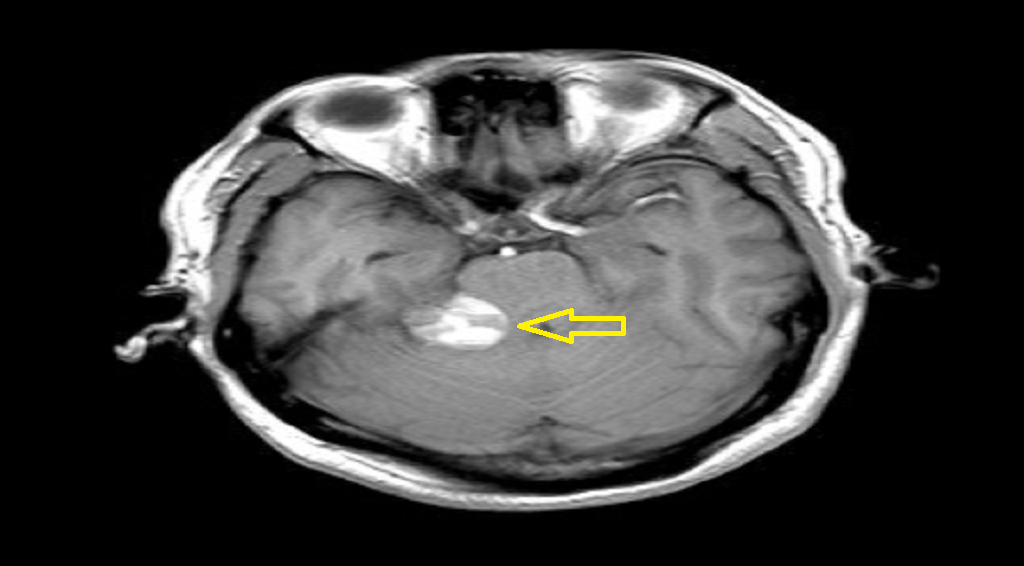

■ 王先生的肿瘤位于右侧桥小脑角区考虑为听神经瘤可能性大,虽然较王女士的肿瘤小,但该肿瘤已严重侵犯王先生内听道,还有瘤内出血现象,必须马上手术。术中手术医师全神贯注在电生理监测下细致地避开重要血管,将肿瘤组织与面听神经、三叉神经分离,成功将肿瘤完整切除。

(术前)